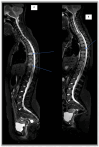

Background/Objectives: Chronic non-bacterial osteomyelitis (CNO) is a rare autoinflammatory disease characterized by chronic sterile uni- or multifocal osteomyelitis. The treatment of CNO is mostly empirical and the outcome of the disease has not yet been standardized. The aims of this study were to correlate clinically active lesions with radiological signs of inflammation and to evaluate the outcomes in terms of symptoms and radiological signs with Whole Body Magnetic Resonance Imaging (WB-MRI) based on the treatment line used. Methods: A retrospective, observational cohort study of 20 CNO patients, recruited from a single tertiary center in southern Italy, was conducted. Patients included in the study were treated based on the "step-up" approach and were guided by the "treat-to-target" strategy as well as by the response to therapy. The outcome measure was stratified into four different groups, defined by a "Delphy consensus", depending on the symptoms and the presence of bone lesions in WB-MRI, compared with the therapy carried out. Results: Pain was the most common presenting symptom of the disease. Only 15% of our patients reported long-term complications. WB-MRI was performed for each patient both at diagnosis and during follow-up. At onset, the site most affected by the disease was the tibia. All patients who reached a 5-year follow-up (30%, n = 6) achieved a complete disease remission. Conclusions: The standardized "step-up" treatment approach in our cohort proved effective in disease management with disease control or remission in nearly 90% of patients at one year from diagnosis.